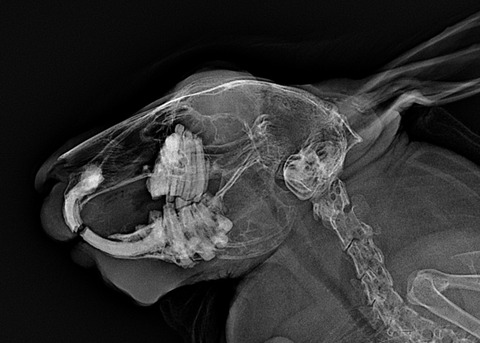

上顎臼歯(上側の奥歯)の歯根が不正なために炎症や感染を起こしてスナッフルの症状が出る時もあります

正常なうさぎの歯根と比べて揃っていない、ガタガタしているのがレントゲンで分かります

重症例や慢性経過の例では、レントゲンで歯根や鼻腔内の異常が無いかを調べます

骨変形を起こして鼻腔内が白くモヤっと見えることがあります